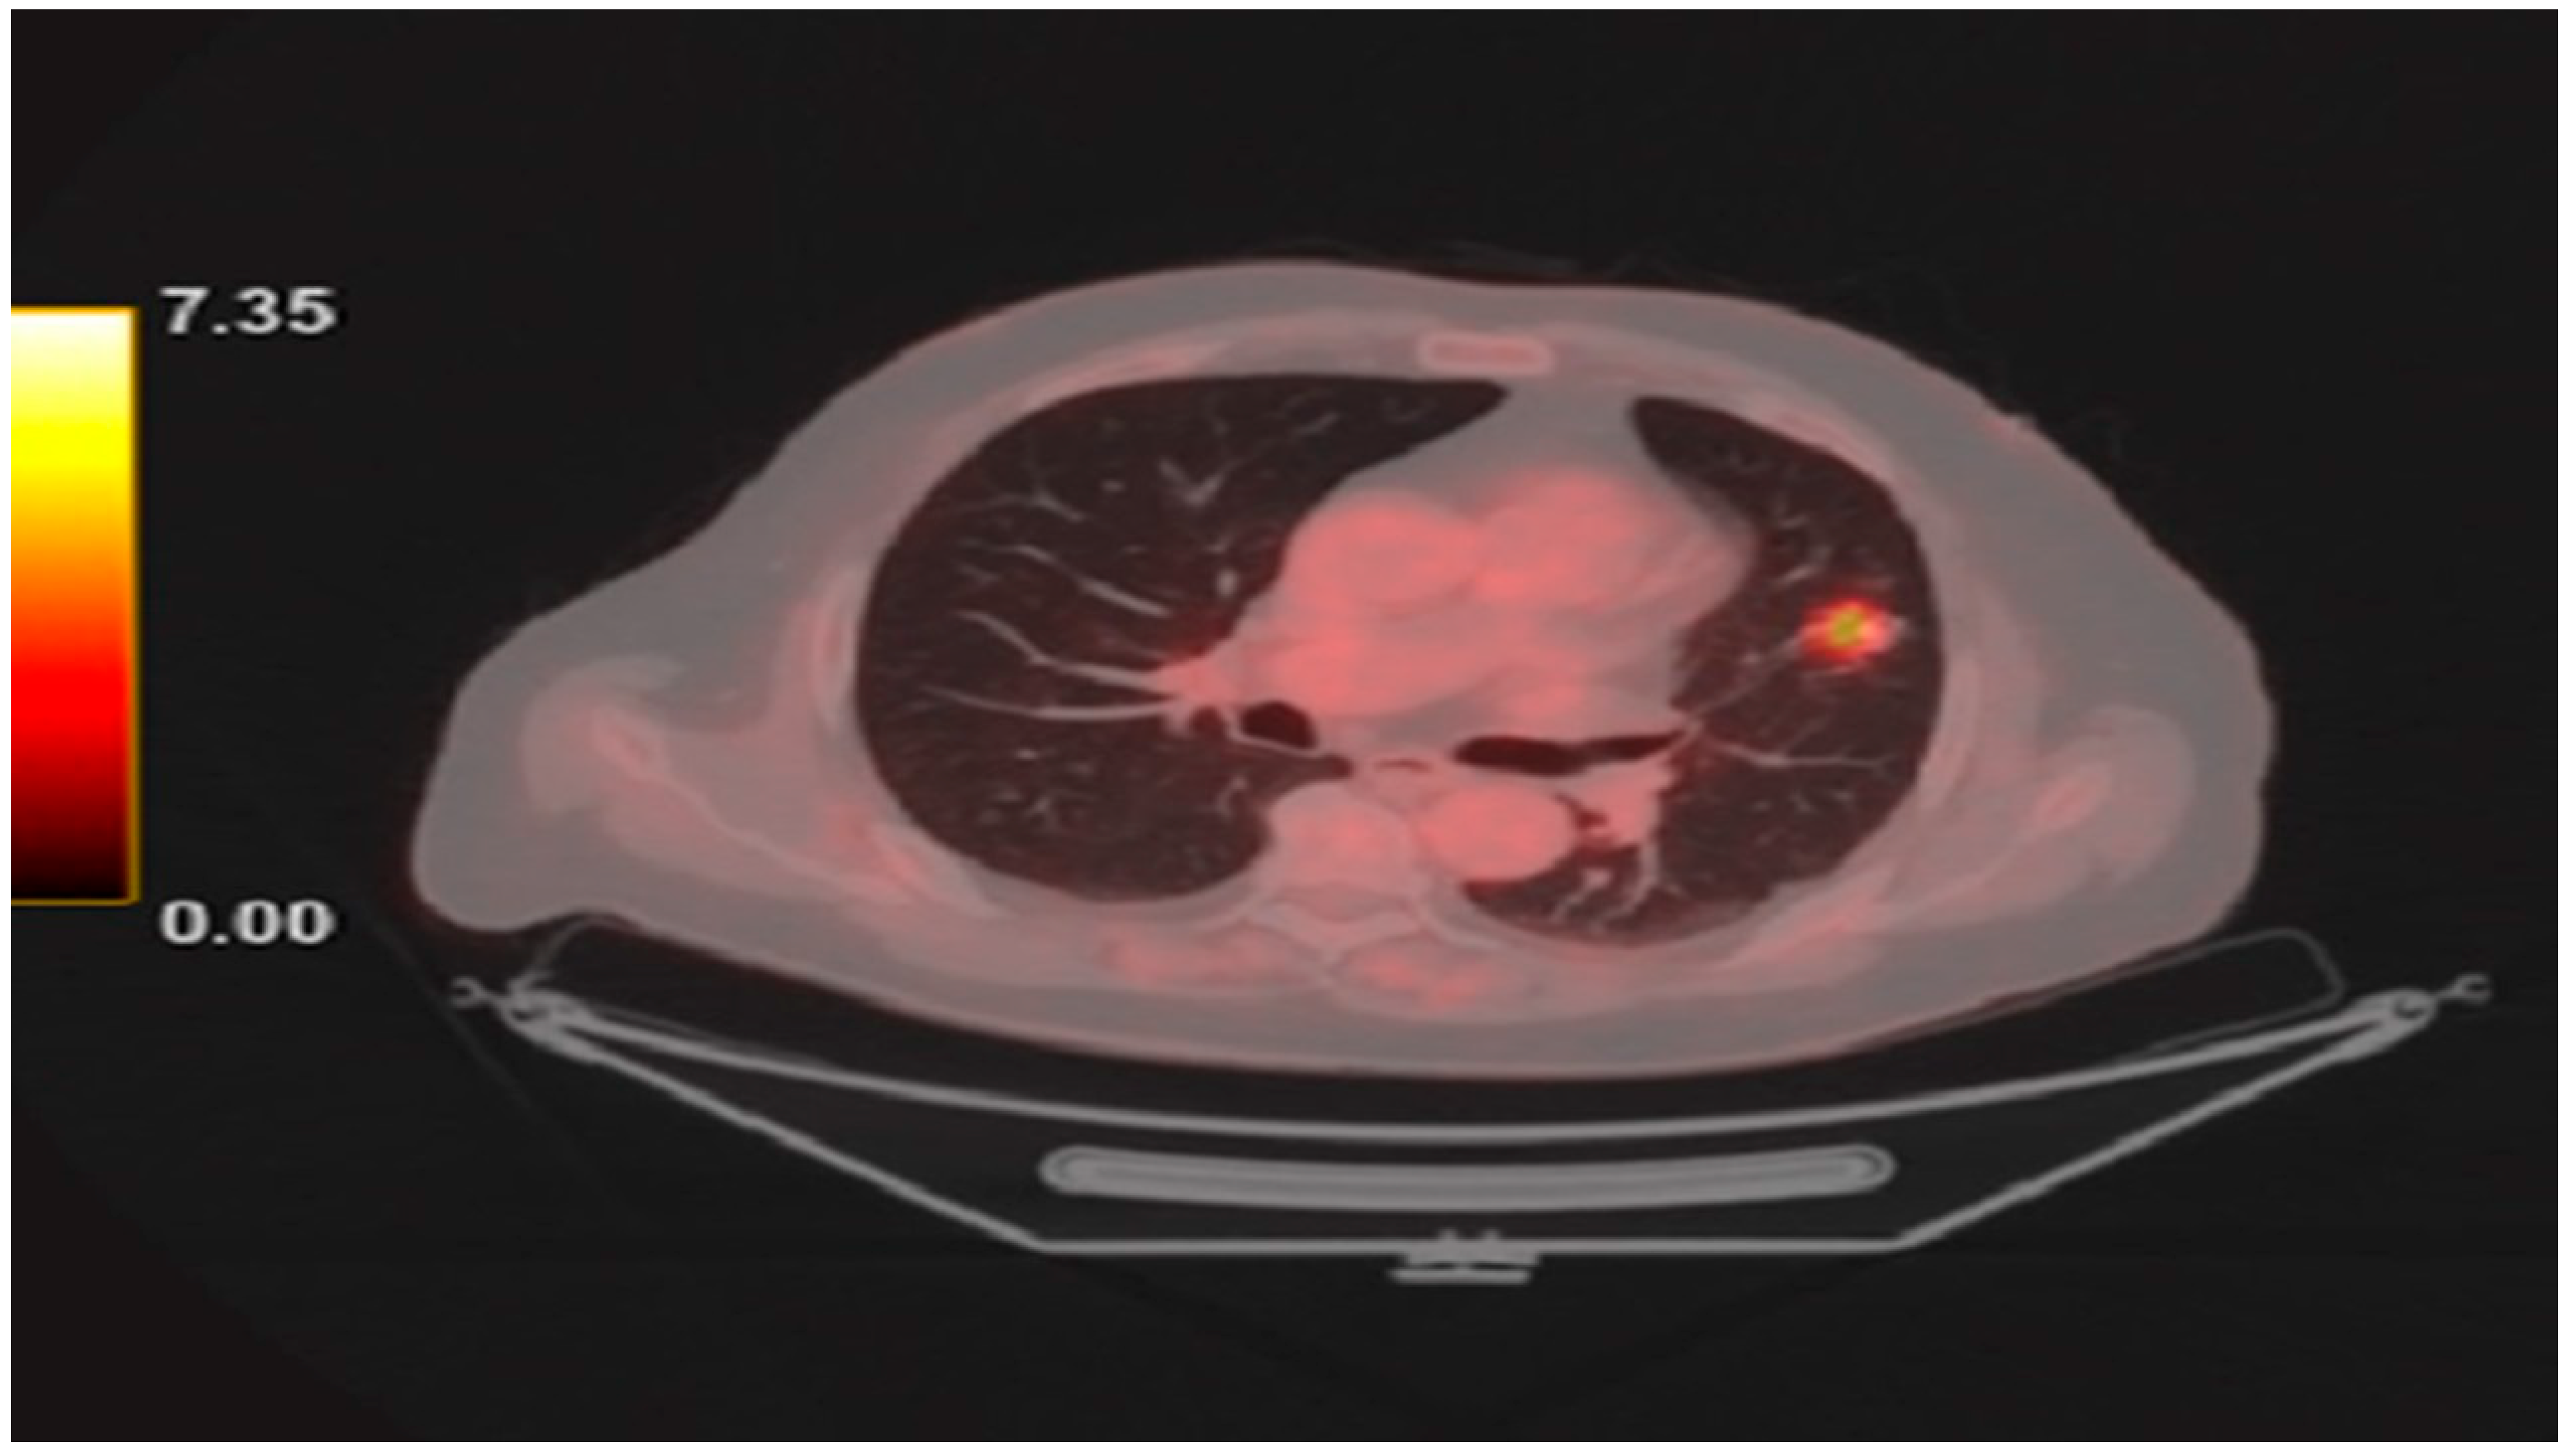

2. Detailed Case Description